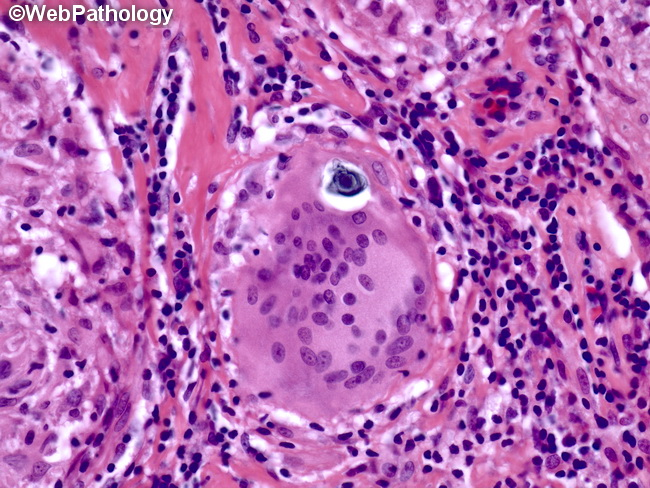

Sarcoidosis is a systemic disorder characterized by widespread, immune-mediated formation of noncaseating granulomas.

- Granuloma formation: Mature granulomas are composed of epithelioid cells and macrophages surrounded by lymphocytes and fibroblasts.

- Th1 cells stimulate the formation of epithelioid cells and multinucleated giant cells by releasing IFN-γ.

- Asteroid bodies: star-shaped, eosinophilic inclusion bodies consisting of various lipids (e.g., from sarcoidosis, foreign body reactions)

- Confirmatory/Gold Standard: Tissue biopsy showing Non-caseating granulomas.

- Schaumann bodies: cellular inclusion bodies consisting of intracytoplasmic calcium and protein with laminar stratification (e.g., sarcoidosis, tuberculosis, Crohn disease, berylliosis)